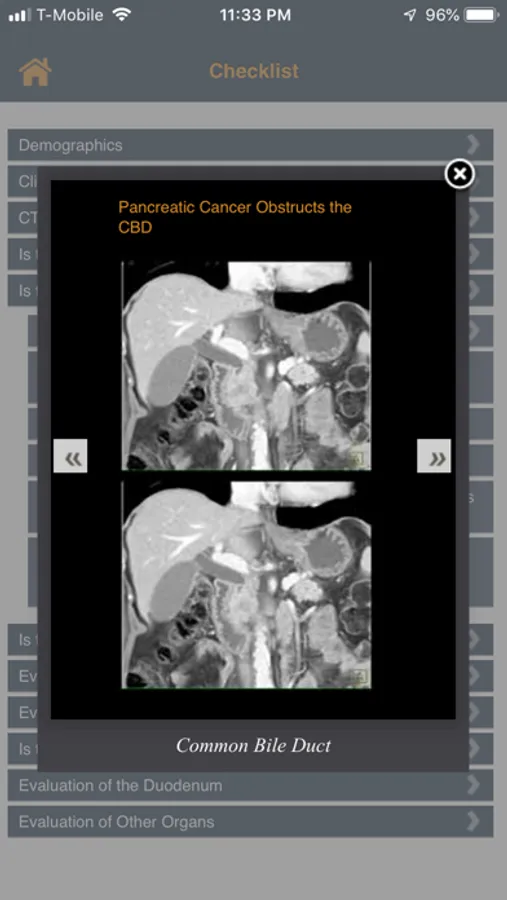

Checklists are a valuable tool when analyzing information and can be extremely valuable in the work flow of a medical professional. There are many factors that Radiologists must consider when evaluating and diagnosing the presence of a pancreatic tumor. The goal of the App is to provide a starting point for the systematic review of the CT scan of the patient with a suspected pancreatic mass. In this App there are a series of topics ranging from exam quality to patient age and sex to whether or not the common duct or pancreatic duct are dilated. Each topic is linked to additional topics or pearls which will help with the differential diagnosis and staging if a pancreatic tumor is present. After "hands on" experience with this program, the user will;